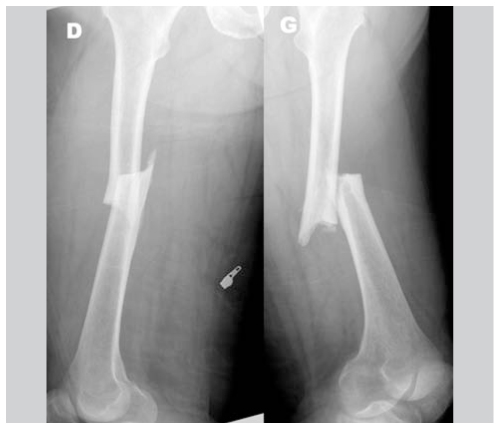

Les fractures atypiques se distinguent des fractures du fémur « classiques » par leur localisation et leurs caractéristiques radiologiques. Ces fractures transverses ou obliques courtes, souvent bilatérales, peuvent survenir sur n’importe quelle partie du fémur entre la partie inférieure du petit trochanter jusqu’au dessus de la zone supracondylienne. Elles surviennent après un traumatisme minime ou même sans traumatisme.